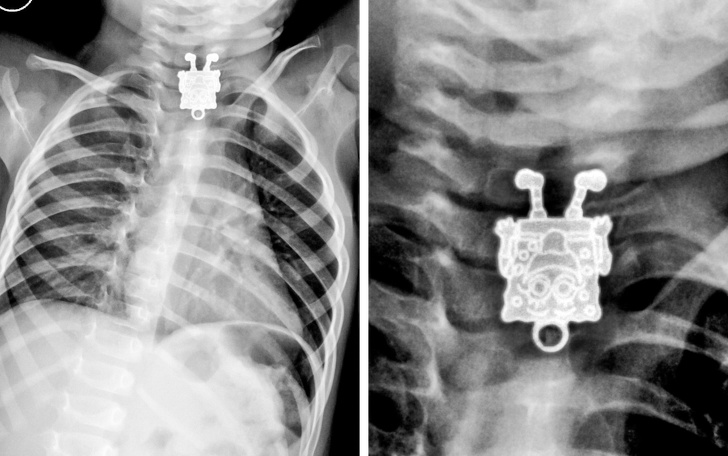

3. Дитина проковтнула підвіску у вигляді Губки Боба